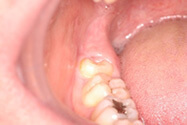

当科では初期の口腔がん(口の中にできる悪性腫瘍)の発見と早期治療に重点をおいています。口腔がんは早期発見・早期治療が重要であり、白板症や紅板症などの前癌病変が、明らかに悪性化する以前に検出可能な粘膜染色を応用し、早期発見・早期治療に努めています。また、悪性腫瘍切除に際しては、術中の迅速病理検査を行い、病理レベルで取り残しのない切除手術を行っています。

ヨード・トルイジンブルー染色法による検査

ヨード生体染色

ヨードは褐色調の液体であり、殺菌効果がある。口腔粘膜にヨードを拭掃した場合、通常観察では、病変の範囲がはっきりしないのに対し、正常粘膜の部分が黒褐色に変色し、病変が浮き上がって見える。

すなわち、ヨード不染部は口腔前癌病変が癌化に至るプロセスで、異型上皮が中等度から高度の段階で発現するのに対し、トルイジンブルー濃染部は高度から発癌の段階で発現するものと考える。

ヨード・トルイジンブルー生体染色

ヨード不染部とトルイジンブルー染色部のそれぞれの発癌過程での染色性の差を利用した方法である。ヨード染色により癌とその周囲の異型上皮を描出して、病変の範囲を確定した後に、いったん脱色して、さらにトルイジンブルー染色を施し、発癌している部分だけを明確に染め分ける方法である。

染色だけで癌あるいは異型上皮と確定診断ができるまでではないが、最初に行うスクリーニングテストとしては大変有効な方法である。